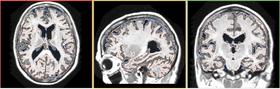

Input Image with Mask

This module takes two input volumes and generate two output volumes. Input Volume is the MR image to be segmented. Input Mask gives the mask within which segmentation is applied. Hard Segmentation is an output label map. And Bias Field is the estimated bias field.